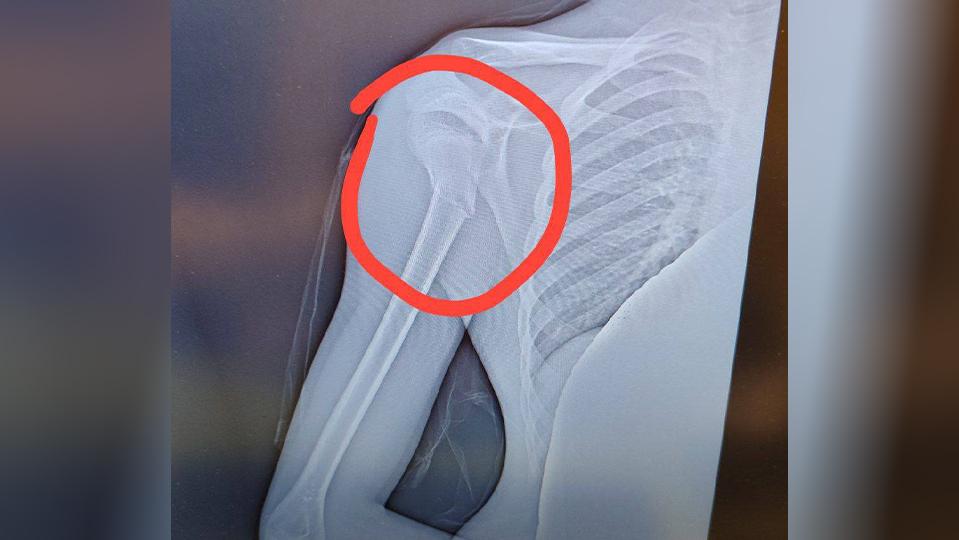

В результате у мальчика диагностировали перелом со смещением.

Как рассказали очевидцы, мужчина не впервые трогает детей. В этот раз нападавший ткнул мальчика лицом в снег, а после сделал подсечку, из-за чего мальчик сломал руку в районе плеча.

Мать пострадавшего заявила, что теперь мальчику предстоит операция и реабилитация. Заявление в полицию также было составлено.